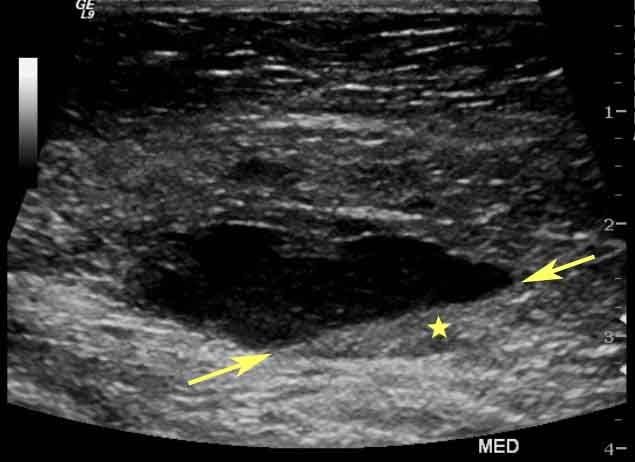

Este examen es indoloro y se realiza de manera externa en la mayoría de los casos, deslizando el transductor sobre el abdomen de la madre. En ciertas situaciones, especialmente en las primeras semanas, se puede realizar un ultrasonido transvaginal para obtener imágenes más claras. Este procedimiento es seguro en todas sus variantes y no implica riesgos para el bebé o la madre.

Además, este examen es útil para detectar complicaciones placentarias, como placenta previa o desprendimiento de la placenta. También evalúa el nivel de líquido amniótico, lo que es crucial para garantizar un entorno saludable para el desarrollo del bebé. Si los niveles de líquido son demasiado altos o bajos, el médico puede tomar medidas para prevenir problemas mayores.

Los médicos suelen recomendar ultrasonidos en diferentes etapas del embarazo según las necesidades de cada caso. El primer ultrasonido se realiza generalmente entre las semanas 6 y 12 para confirmar el embarazo y calcular la edad gestacional. En el segundo trimestre, un ultrasonido de anatomía permite evaluar el desarrollo estructural del bebé y descartar malformaciones.

En el tercer trimestre, los ultrasonidos son útiles para monitorear el crecimiento del bebé y la posición del feto. También se realizan para evaluar el estado de la placenta y el líquido amniótico. Estos exámenes permiten planificar el parto de manera segura y minimizar riesgos.